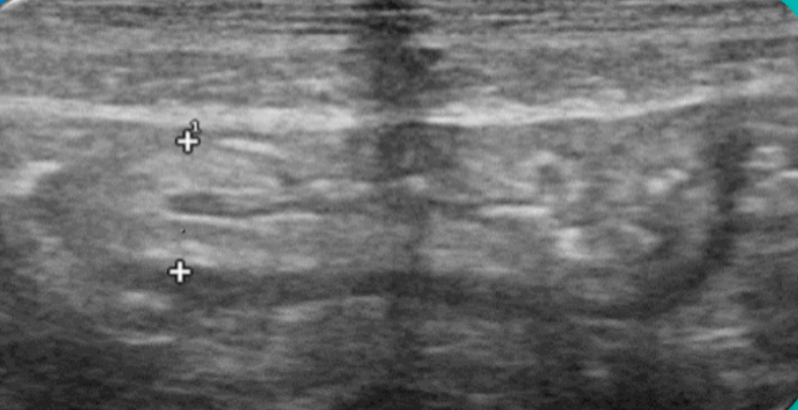

Expondremos la utilidad de la EC como herramienta en el manejo de los pacientes con diferentes tipos de dolor que atiende el Médico de Familia en las consultas diarias, urgentes, e incluso en los domicilios, en diversos escenarios clínicos a los que podemos enfrentarnos en nuestra práctica clínica habitual, desde un dolor visceral (abdominal, torácico, urológico o ginecológico), un dolor músculo-esquelético (traumático o no, con sospecha de fractura u osteoartrósico incapacitante), un dolor vascular (sospecha de trombosis venosa profunda, trombosis arterial aguda, aneurismático); ayudando a obtener una información crucial con un método no invasivo que nos ayudará a reducir la incertidumbre y orientar mejor el diagnóstico de nuestros pacientes e incluso nos podrá ser muy útil como herramienta con fines terapéuticos como en el caso de las infiltraciones ecoguiadas.

En nuestra experiencia como Centro de Salud que utiliza de forma rutinaria la Ecografía clínica, hemos visto un importante avance en nuestra capacidad resolutiva en muchos casos, mejorando el diagnóstico diferencial de los diferentes tipos de dolor, su abordaje terapéutico precoz, e incluso ayudando a los pacientes a una mejor comprensión de su patología.

Consideramos la Ecografía clínica como una herramienta de gran utilidad en la consulta de Atención Primaria, que puede aportar gran ayuda al Médico de Familia en la toma de decisiones, ayudando a obtener diagnósticos diferenciales precoces y que también ayuda a agilizar las derivaciones pertinentes al conseguir en muchos casos un enfoque diagnóstico más preciso.